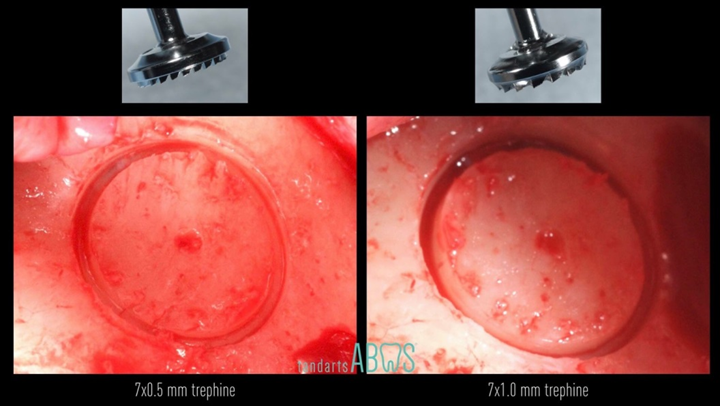

Klinikinis atvejis: Vėlyvoji implantacija: viršutinio žandikaulio ančio dugno elevacija, implanto sriegimas ir kraštinė kaulo regeneracija;

- Dr. Irfan Abas klinikinis atvejis -

Vėlyvoji implantacija, ančio dugno elevacija, ančio dugno elevacija atviru būdu, kraštinė kaulo regeneracija, Dr. Irfan Abas, AnyRidge, MiLA chirurginis rinkinys, kaulo regeneracija;

AnyRidge implantų sistema, MILA chirurginis rinkinys;